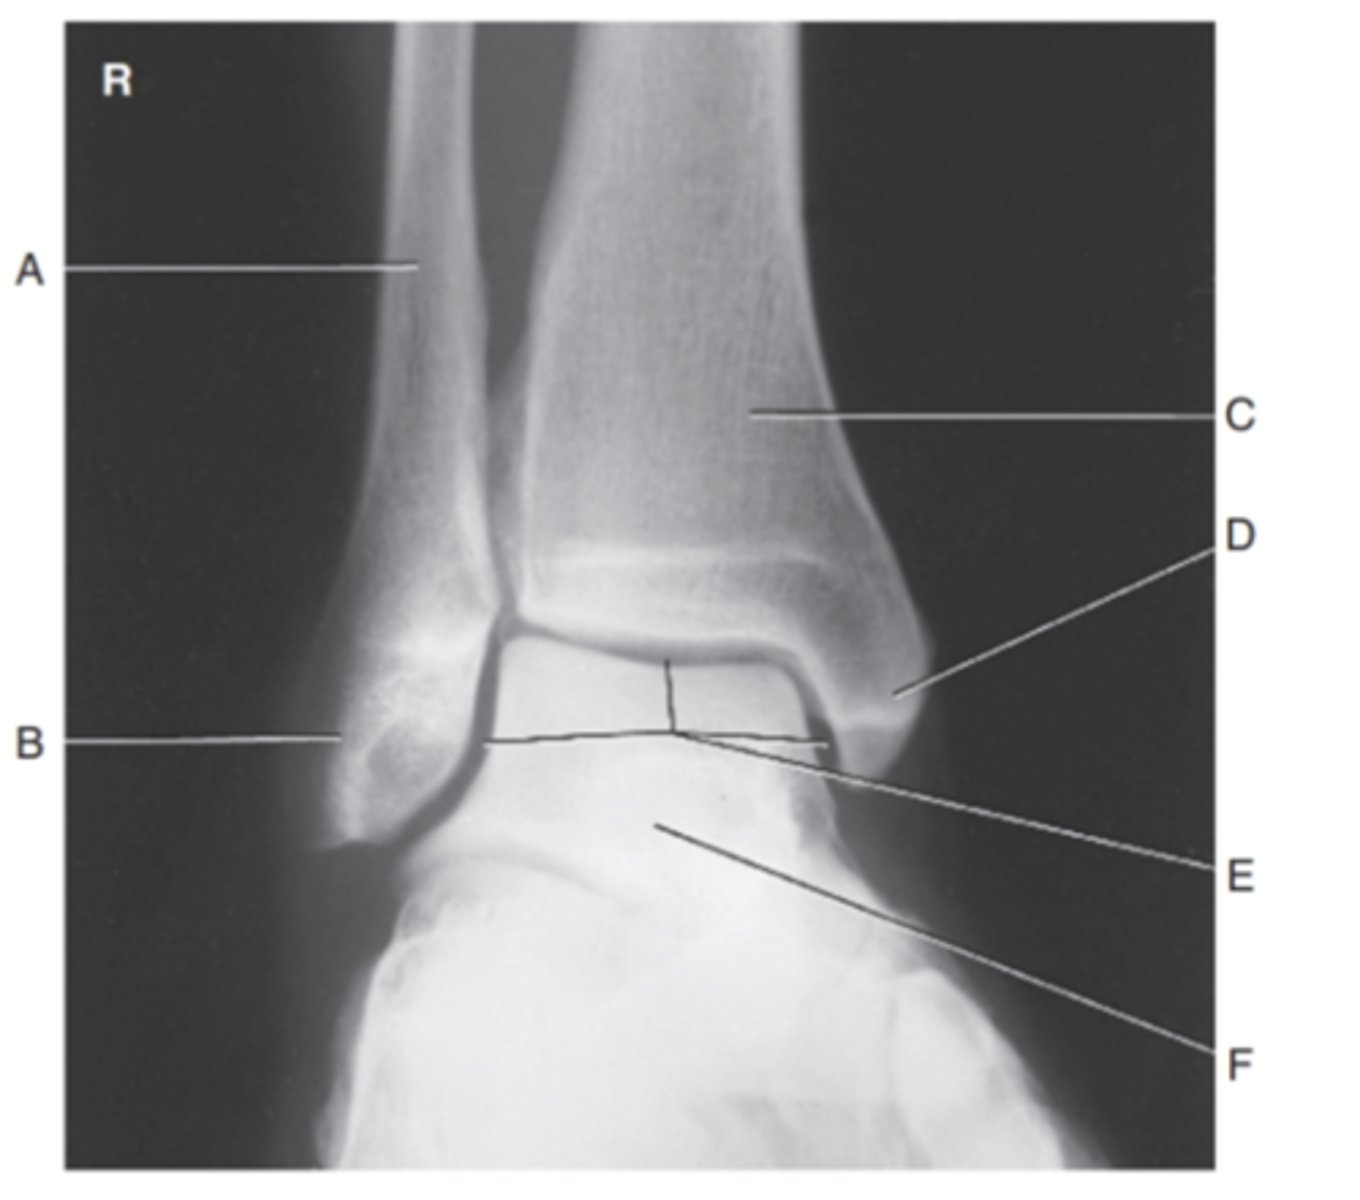

(AP ANKLE) what is A?

fibula

what is B?

tibiotalar joint

what is C?

lateral malleolus

what is D?

tibia

what is E?

medial maleolus

what is F?

talus